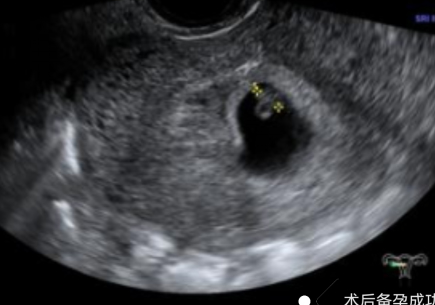

幾個(gè)月前,陳女士(化名)突發(fā)不規(guī)則陰道出血癥狀,且出血持續(xù)多天未見(jiàn)緩解,身體不適與生育焦慮雙重壓力下,前往我院就診,尋求專業(yè)診療方案。不規(guī)則陰道出血是婦科臨床的高頻癥狀,其背后病因復(fù)雜,可能潛藏著子宮內(nèi)膜息肉、黏膜下肌瘤、子宮內(nèi)膜增生等多種病變。若未能及時(shí)明確診斷并采取干預(yù)措施,不僅會(huì)嚴(yán)重影響患者日常生活質(zhì)量,更可能對(duì)生育功能造成不可逆的潛在威脅。針對(duì)該患者的病情,婦科胡菊英副主任帶領(lǐng)婦科團(tuán)隊(duì)展開(kāi)全面評(píng)估,最終確定宮腔鏡手術(shù)為最佳診療方案。該技術(shù)無(wú)需開(kāi)刀,可經(jīng)人體自然腔道進(jìn)入2025-11-10

-